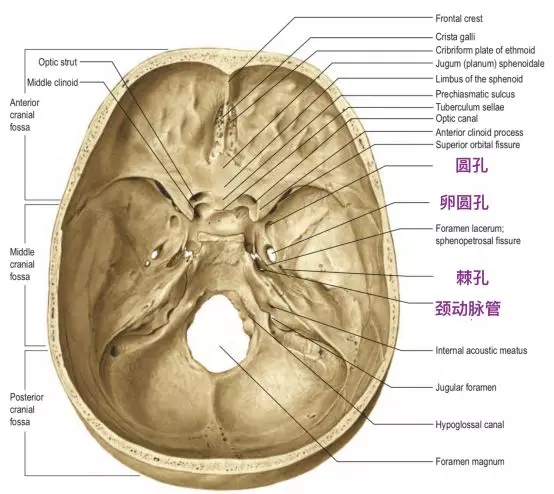

从颅内中颅窝底看,蝶骨大翼包含三个恒定的孔隙和其他多个不恒定的孔隙。三个恒定的孔隙从前向后依次是圆孔、卵圆孔和棘孔。圆孔位于三个孔的最前方,正好位于眶上裂内侧末端的下方,圆孔内走行有三叉神经的第二支上颌神经。卵圆孔内位于中间,走行有三叉神经的第三支下颌神经和脑膜副动脉。棘孔内走行脑膜中动脉。

这三个孔隙的向下方穿过颅底后的开口位置是不同的。卵圆孔和棘孔均向下开口于颅底底面,而圆孔向前外侧,开口于颅骨外表面的深部间隙翼腭窝。翼腭窝后壁上的两个开口,分别是圆孔和翼管。翼管内走行翼管神经和翼管动脉。

圆孔连接中颅窝底和翼腭窝,而翼管连接翼腭窝和破裂孔。圆孔位于翼管的上、外侧。

颅骨底面示意图,显示圆孔、卵圆孔和棘孔的位置(Standring, 2016)。